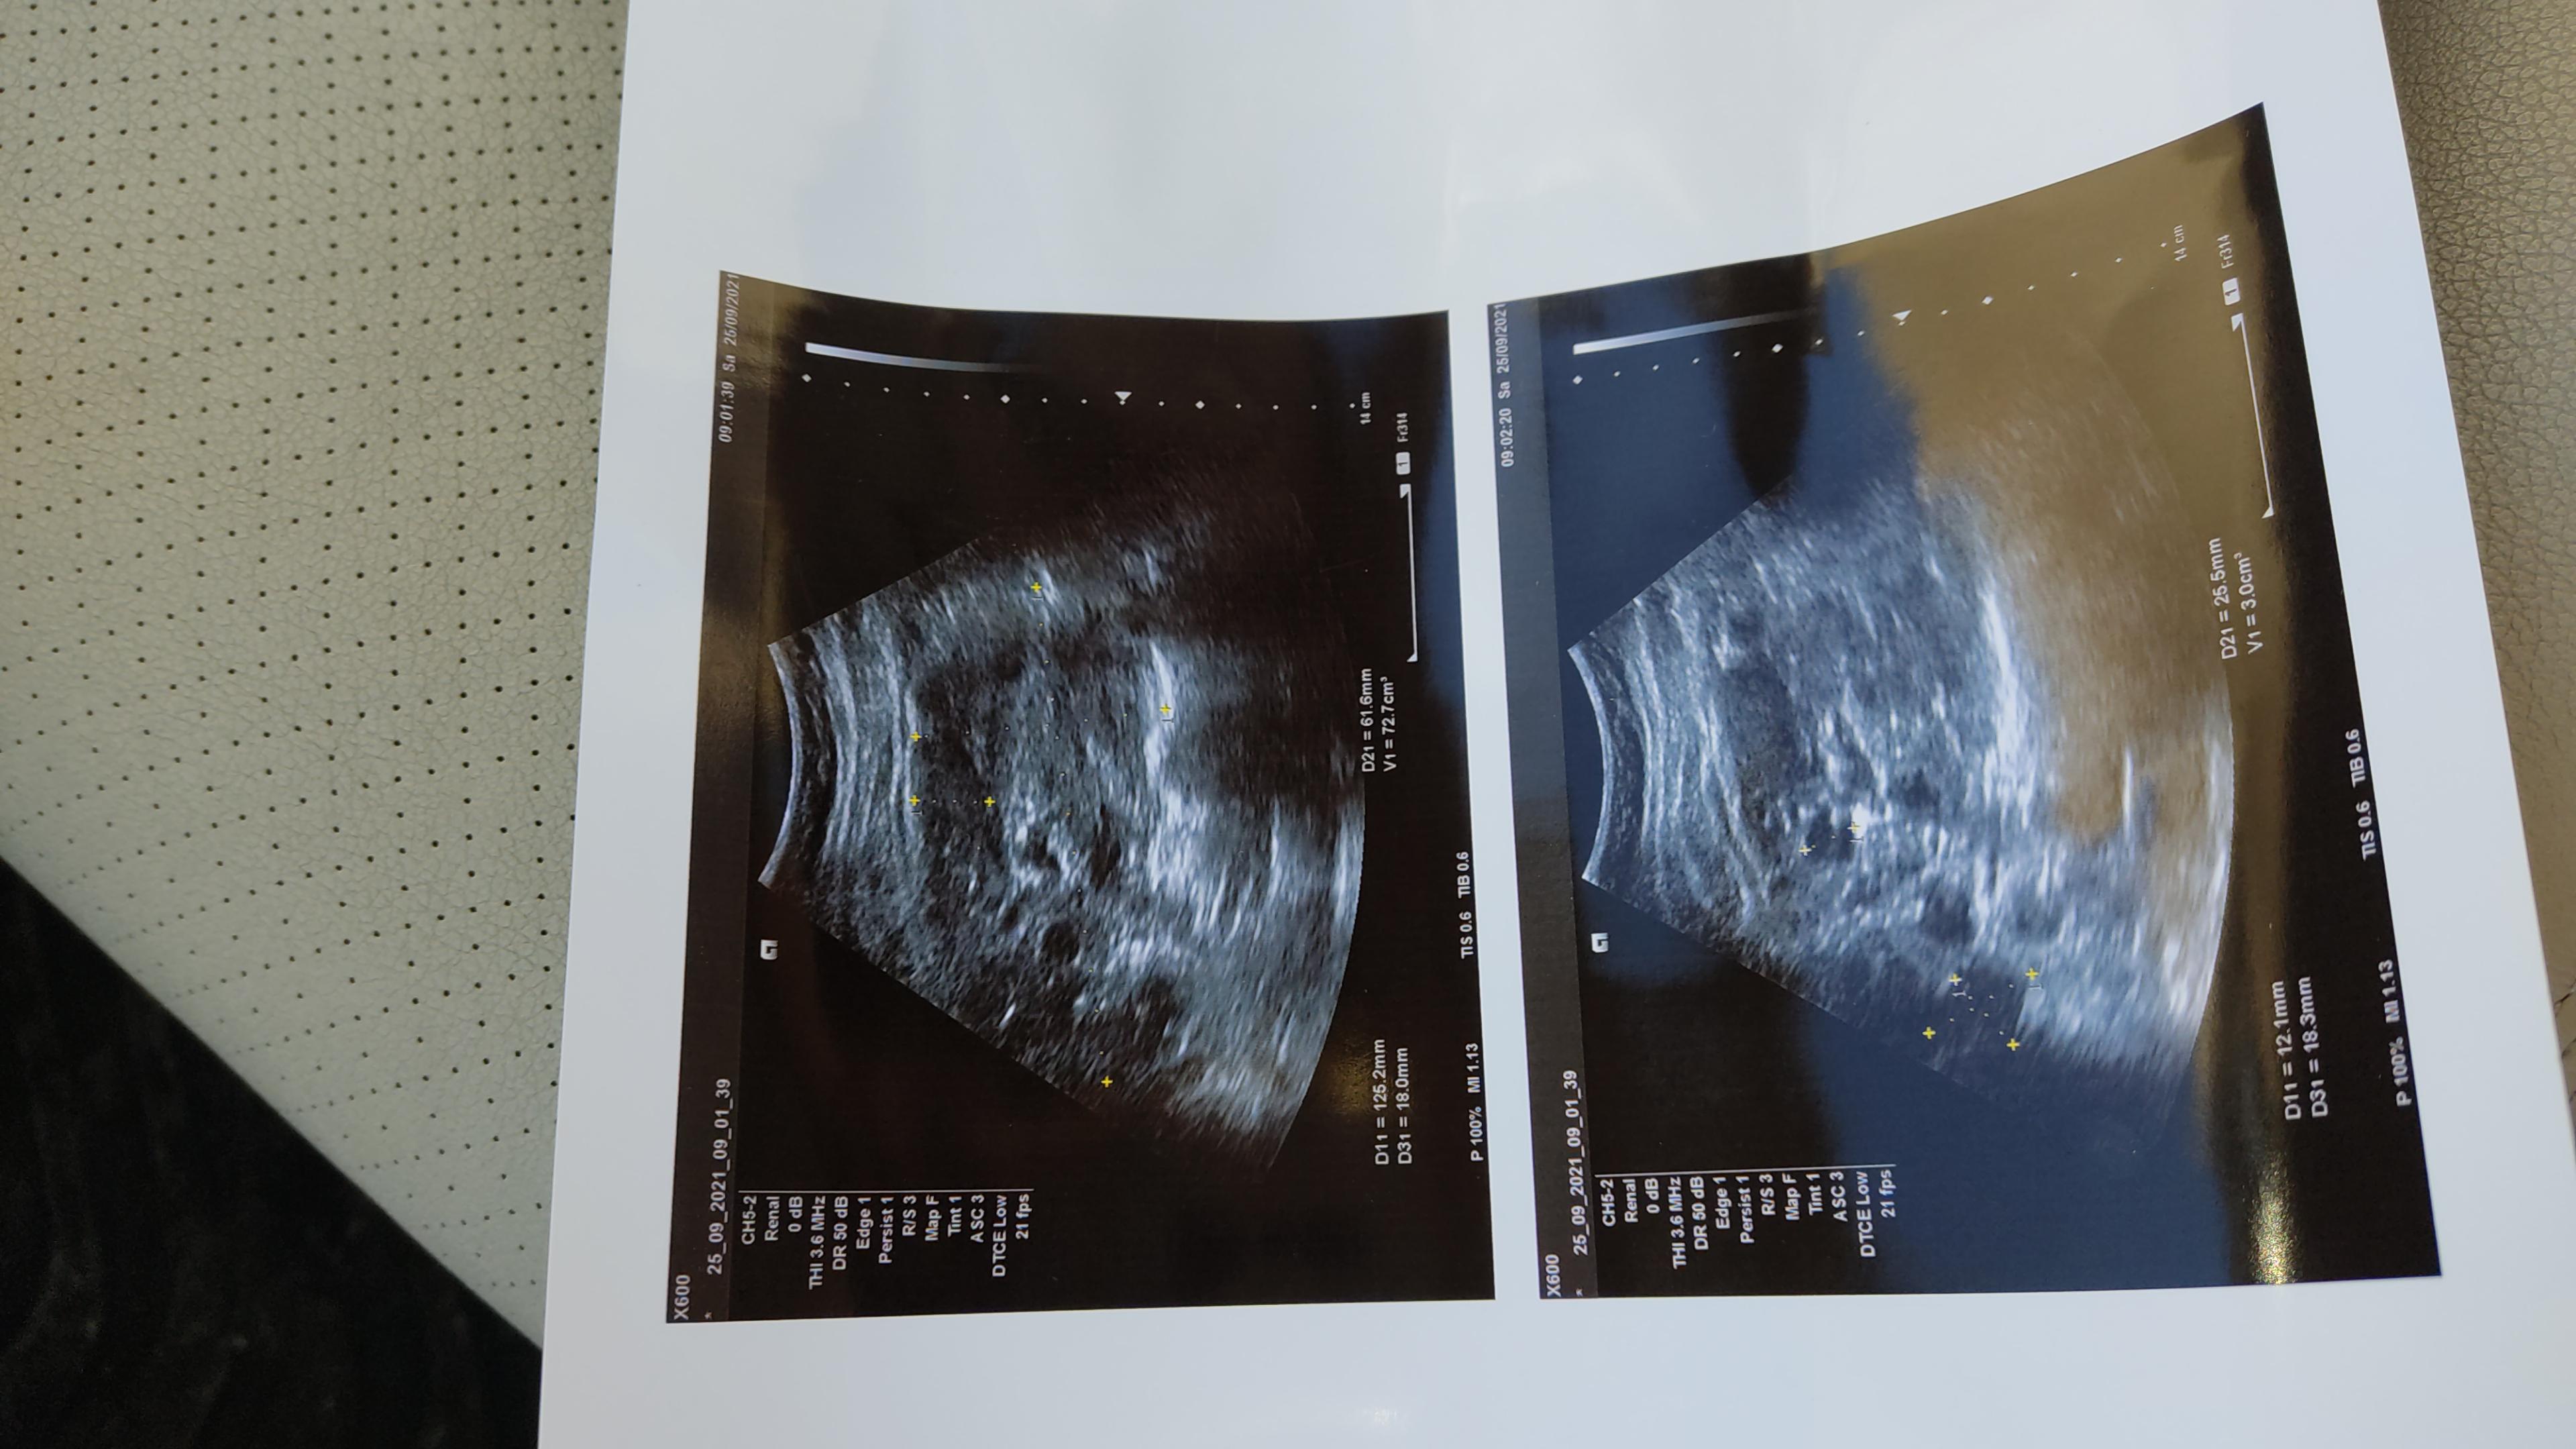

Здравствуйте! Сама являюсь врачом, но другого профиля. Мне 35 лет. Раньше в детстве были частые обострения хронического пиелонефрита. Во взрослом возрасте проблем не было. Во время второй беременности начало повышаться давление, и через месяц в анализах мочи появился белок. Через 3 месяца после родов проведено УЗИ почек, а там множественные кисты. Поликистозом почек в роду никто не болел. Подскажите, пожалуйста, может ли эта картина свидетельствовать о простых, но множественных кистах или же заключение возможно и другое? В голове мелькают разные мысли, в общем, как у врача - и мультилокулярная киста почки, и эхинококкоз, и все тот же полликистоз,, и даже кистозная форма рака. Заранее спасибо за ответ!

Здравствуйте! В первую очередь надо сделать мультиспиральную коипьютерную томографию почек и мочеточников с контрастированием( если позволяет уровень креатинина). Если креатинин повышен - без контрастирования.(УЗИ органов брюшной полости предположительно сделано?) По результатам - обязательно консультация нефролога. Если впоследствии ещё останутся вопросы по тактике, мы готовы Вам помочь на базе наших клиник в организации персонифицированной консультации( в том числе - дистанционной).